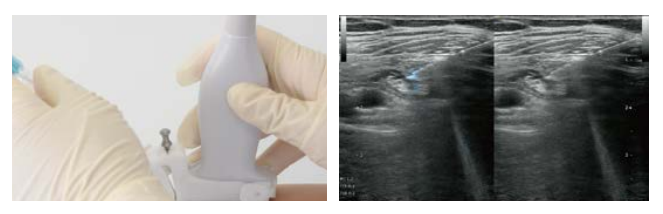

为了满足临床领域的特定需求,真正能够起到精确诊断,简化操作,优化工作流程,HS1 配备了 SNV 穿刺针增强功能。与 X 线不同,超声诊断强调实时性。例如,临床医生在实施超声引导的操作时,要了解针在 实时操作时的具体位置。

应用了“蓝光”技术的 SNV 穿刺针增强功能,在神经阻滞、血管内置管等临床操作中,能清晰的看到针的行进过程。无论是角度很大的平面内进针,还是平面外进针, 这个功能都大大提高了操作的准确性与安全性。